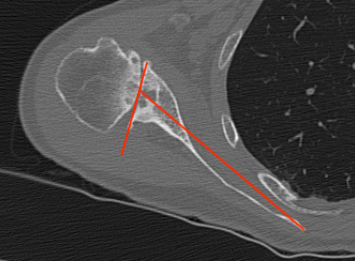

Chalmers et al. J Should Elbow Surg 2017

- 14 B2 glenoids

- glenoid version measurement accurate if > 50% of the scapula width included

a. Friedman method

- tip of the medial border of the scapula to the midpoint of the glenoid fossa

b. Scapula body method

- intersection of the scapula body axis and the glenoid surface

- 3o difference in measurement of glenoid version between the two

- excellent reliability for both measurement techniques